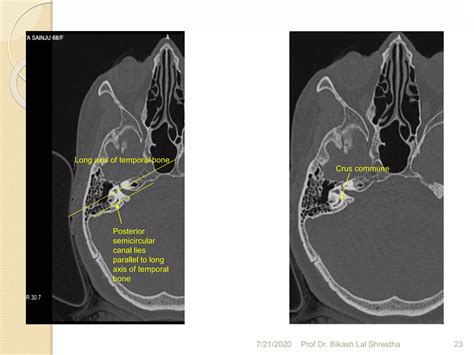

• The petrous part: This dense, pyramid-shaped portion houses the inner ear structures, including the cochlea and vestibular system.

• The mastoid part: Located behind the ear, it contains air cells and the mastoid antrum.

The Ct Temporal Bone scan is particularly useful in visualizing these intricate structures due to its high-resolution imaging capabilities. This makes it an invaluable tool for diagnosing various conditions affecting the temporal bone.